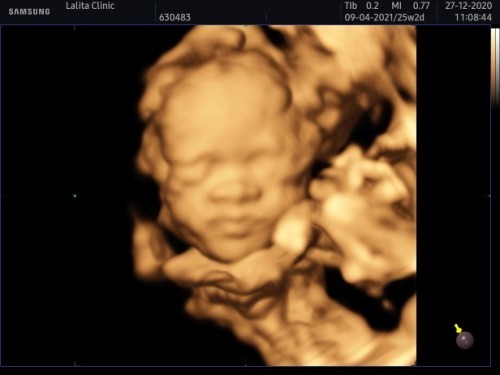

ภาพอัลต้าซาวด์4มิติ ได้ลูกสาวจ้า ขอดูคนที่ได้ลูกสาวหน่อยค่ะ

วันนี้ไปอัลตร้าซาวด์4มิติมาค่ะ พร้อมแบบMFMดูความพิการของทารก ที่คลินิกหมอลลิตาปากน้ำน้องแข็งแรงปกติสมส่วนทุกอย่างค่ะ 25สัปดาห์ 3วัน ตอนนี้นหนัก640กรัมค่ะ ตอนยังไม่ซาวมีแต่คนทักว่าผช.แน่ๆสิวเห่อเต็มหน้า แต่พอไปซาวด์มา #คุณหมอบอกว่าน้องเป็นผู้หญิง100%คะแม่ แม่ดูตอนเขาซาวด์หว่างขาเห็นเป็นกลีบๆน่าจะชัวร์นะค่ะ แม่ก็แอบดีใจจ้า เพราะอยากได้ผู้หญิง555. #ท้องแรก #ทีมเมษา2021